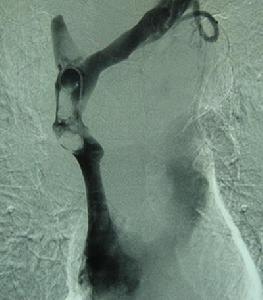

肝靜脈阻塞綜合徵病理圖肝靜脈阻塞綜合徵(hepatic vein obstruction syndrome)又稱Budd- Chiari綜合徵(BCS)、Chiari綜合徵Rokitansky綜合徵、肝靜脈血栓形成綜合徵、肝靜脈反流障礙綜合徵等。由於某種原因而致肝靜脈或(和)下腔靜脈閉塞閉塞可先發生於肝靜脈而後延伸到下腔靜脈,或與之相反。1970年Hirooka將肝靜脈阻塞綜合徵征分為7型,但就手術水平,有人根據下腔靜脈阻塞的特徵、肝靜脈受累的情況將Hirooka分型簡化為4型。1846年Budd首先記載了肝靜脈血栓形成,1898年Chiari報導13例,並將肝靜脈阻塞綜合徵征作為獨立的類型。

Budd-Chiari綜合徵是指肝靜脈乾和(或)下腔靜脈的肝靜脈入口處有一段完全或不完全阻塞而引起的徵候群。本綜合徵的病因有原發及繼發二種。原發性者主要是先天性血管異常,如下腔靜脈膜性阻塞所致的肝靜脈阻塞。繼發性者可由血液凝固性積升高疾病(如紅細胞增多症),肝癌及腹腔腫瘤,腹部創傷及某些口服避孕藥等引起的該段靜脈血栓形成所致。醫學教.育網蒐集整理病理變化主要為肝淤血,肝細胞萎縮、變性以至壞死。此外,還有肝出血,即淤於肝竇內的紅細胞進入竇外壓力較低的Disse腔及萎縮的肝板內。慢性病例則發展為淤血性肝硬變。

肝靜脈阻塞綜合徵病理圖急性BCS突然發生腹痛腹部迅速膨脹,體格檢查可發現黃疸,肝大伴壓痛,大量腹水,但肝頸靜脈回流徵陰性血壓低,小便少,血磺溴酞鈉(BSP)瀦留,轉氨酶上升。手術時見肝大,呈紫藍色。病人大部死於循環失常、肝功能衰竭或胃腸出血。慢性BCS時,症狀發生較慢,可有黃疸脾腫大,蜘蛛痣。